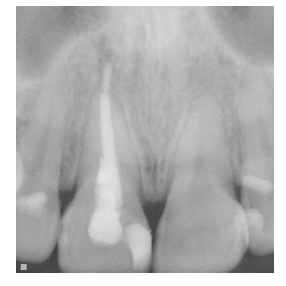

本報告はヘルシンンキ宣言を順守し, 行った. 初診から治療終了時までの顔面写真, 口腔 内写真, エックス線写真等の資料, ならびに各種診察結果, 分析結果, 診断結果, 治療方針, 治療経過等を記した書類を本症例報告に使用することを患者本人に説明し, 論文に掲載す る承諾を得た. 患者:24 歳3 カ月, 女性. 主訴:1 本だけ色の異なる歯があるので, 白くしたい. 既往歴:局所麻酔の異常なし, 全身疾患, 服薬などの, その他の特記事項なし. 現病歴:11 歯は約7 年前に, 一過性の冷水痛を覚え他院を受診した. 齲蝕症との診断によ り, コンポジットレジン修復を受けた. その後問題なく経過していたが, 約4 年前 に自発痛が生じ, その後, 次第に色が変わり気になってきたという. 現症:11 歯は歯冠全体が一様に変色し, 近遠心に3 級コンポジットレジン修復が施されて いたが, 修復物辺縁に褐線が認められた(図1). VITA classical シェードガイド (VITA)による視感比色法ではA3 よりも彩度が高かった(図2). 嗜好品としては, 喫 煙はないがコーヒーを1 日当たり2~3 杯程度飲んでいるという. エックス線検査で は根管充填状態は良好で, 根尖部の異常は認められなかった(図3).

図3 初診時の

エックス線写真